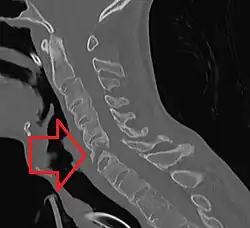

Cervical spine showing ankylosis (fusion) -

The earliest changes demonstrable by plain X-ray shows erosions and sclerosis in sacroiliac joints. Progression of the erosions leads to widening of the joint space and bony sclerosis. X-ray spine can reveal squaring of vertebrae with bony spur formation called syndesmophyte. This causes the "bamboo spine" appearance. A drawback of X-ray diagnosis is the signs and symptoms of AS have usually been established as long as 7–10 years prior to X-ray-evident changes occurring on a plain film X-ray, which means a delay of as long as 10 years before adequate therapies can be introduced.[26]

Options for earlier diagnosis are tomography and MRI of the sacroiliac joints, but the reliability of these tests is still unclear.

Surgery

In severe cases of AS, surgery can be an option in the form of joint replacements, particularly in the knees and hips. Surgical correction is also possible for those with severe flexion deformities (severe downward curvature) of the spine, particularly in the neck, although this procedure is considered very risky. In addition, AS can have some manifestations that make anesthesia more complex. Changes in the upper airway can lead to difficulties in intubating the airway, spinal and epidural anesthesia may be difficult owing to calcification of ligaments, and a small number of people have aortic insufficiency. The stiffness of the thoracic ribs results in ventilation being mainly diaphragm-driven, so there may also be a decrease in pulmonary function.